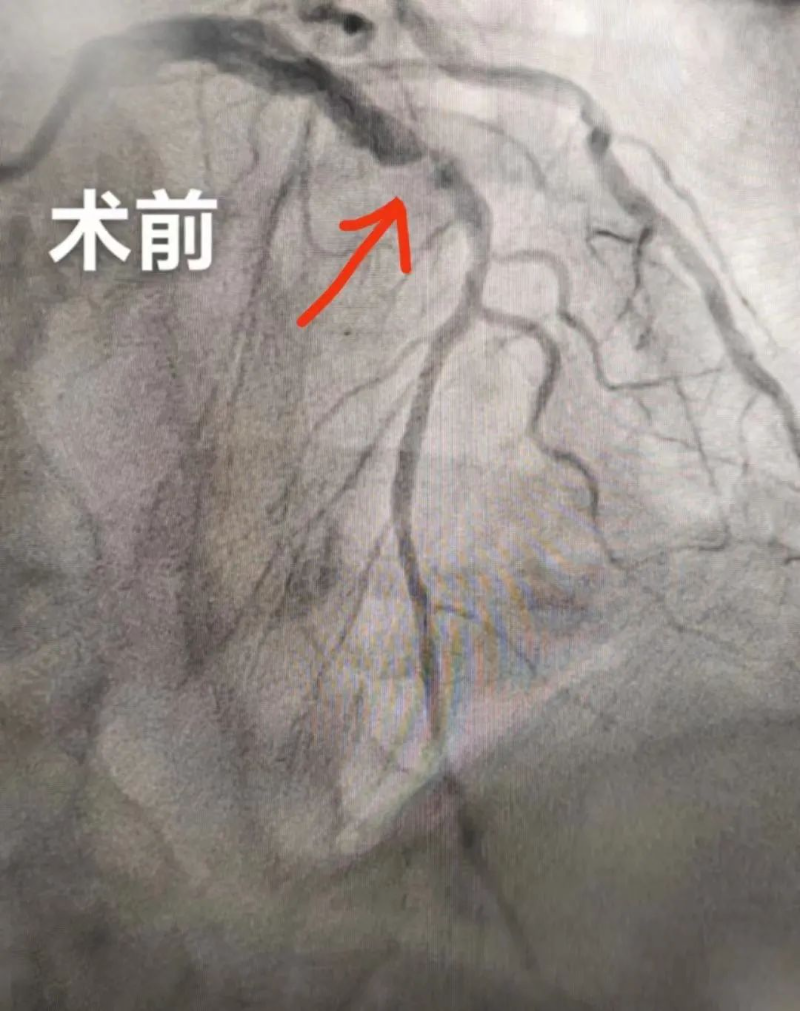

9月19日晚上,新院心血管内科为一名急性广泛前壁心肌梗死患者行支架植入术,成功挽救了患者的生命,阻止了病情的继续恶化,这也是我院整体搬迁至新院后的首台介入手术,标志着新院介入室正式启用,迈入一个新起点。

家住杨村80岁的李大爷(化名)胸口疼痛呈压榨性,疼痛症状持续不能缓解。家属送李大爷到杨侨镇卫生院就诊,心电图结果提示广泛前壁ST段抬高,杨侨镇卫生院通过分级转诊微信工作群传送心电图,经我院心血管内科杨世映副主任医师远程会诊,确诊为急性广泛前壁心肌梗死,建议绿色通道双绕行急诊PCI。

随后,杨侨镇卫生院立即护送李大爷转诊至我院,送入介入室,介入团队快速完成急性心梗支架植入术,门球时间20分钟。术后,李大爷转危为安。